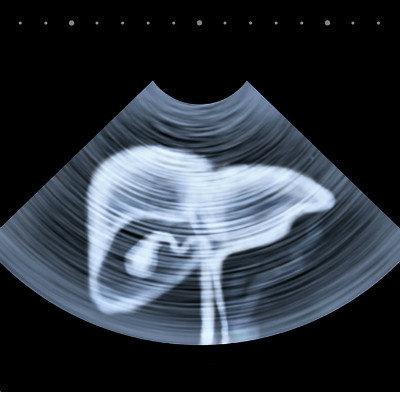

Can early liver cirrhosis be cured?

When the discovery of early cirrhosis, to grasp the opportunity of early treatment, because early cirrhosis in clinical without any prominent symptoms, so when many patients with cirrhosis found, it is late cirrhosis. Therefore, early diagnosis of liver cirrhosis is very important. It is suggested that liver biopsy should be performed in patients with liver disease, virus carriers, fatty liver disease and alcoholic liver disease who have not been cured for a long time, so as to predict liver cirrhosis in advance and avoid the deterioration of liver cirrhosis.